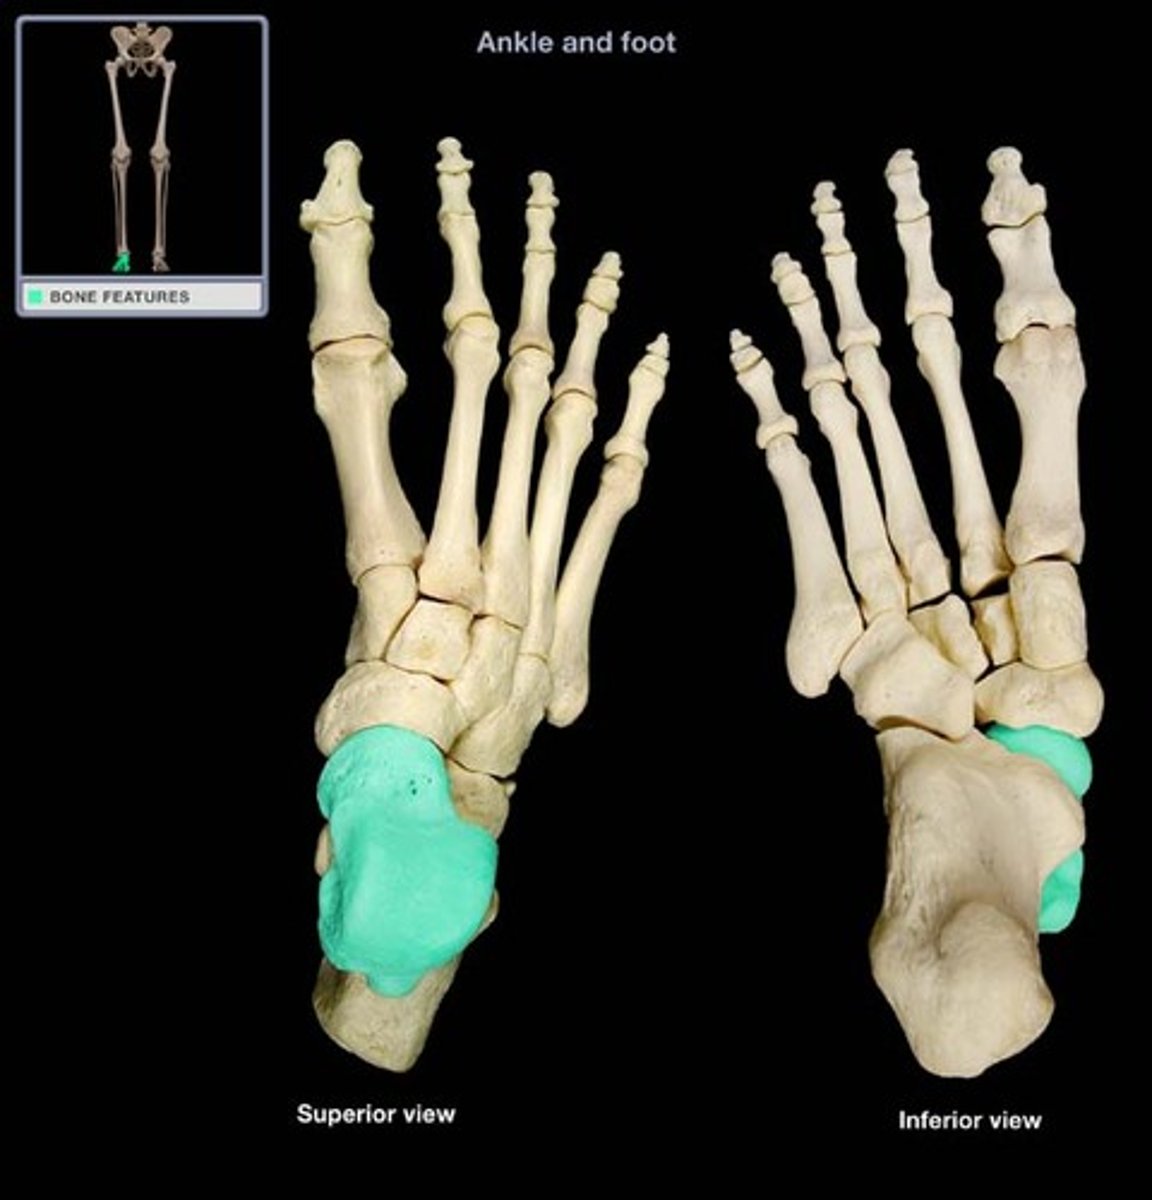

talus